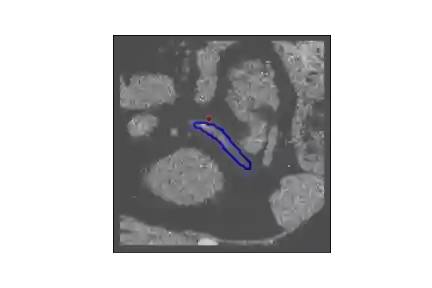

The human annotations are imperfect, especially when produced by junior practitioners. Multi-expert consensus is usually regarded as golden standard, while this annotation protocol is too expensive to implement in many real-world projects. In this study, we propose a method to refine human annotation, named Neural Annotation Refinement (NeAR). It is based on a learnable implicit function, which decodes a latent vector into represented shape. By integrating the appearance as an input of implicit functions, the appearance-aware NeAR fixes the annotation artefacts. Our method is demonstrated on the application of adrenal gland analysis. We first show that the NeAR can repair distorted golden standards on a public adrenal gland segmentation dataset. Besides, we develop a new Adrenal gLand ANalysis (ALAN) dataset with the proposed NeAR, where each case consists of a 3D shape of adrenal gland and its diagnosis label (normal vs. abnormal) assigned by experts. We show that models trained on the shapes repaired by the NeAR can diagnose adrenal glands better than the original ones. The ALAN dataset will be open-source, with 1,594 shapes for adrenal gland diagnosis, which serves as a new benchmark for medical shape analysis. Code and dataset are available at https://github.com/M3DV/NeAR.